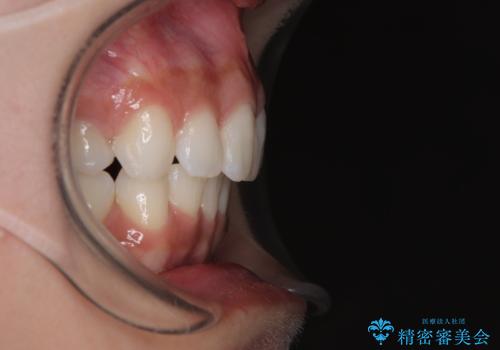

左右ともに奥歯の咬み合わせに問題があり、上顎臼歯が前方位にある状態で、結果として上顎前歯全体が前方位かつ叢生になっていました。

補助装置を用いて上顎歯列全体を後方に移動させ、下顎は左右で抜歯する小臼歯を変えることで、左右の咬み合わせをより理想的な位置となるように計画しました。